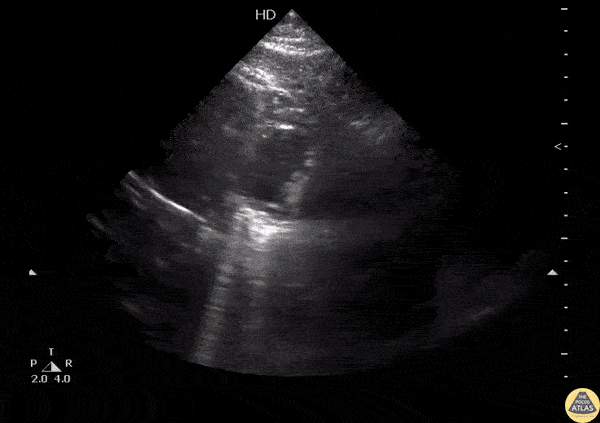

This subcostal view shows cysts located on the pericardium. A benign and rare finding to be aware of while performing an echo. Image courtesy of Robert Jones DO, FACEP @RJonesSonoEM Director, Emergency Ultrasound; MetroHealth Medical Center; Professor, Case Western Reserve Medical School, Cleveland, OH View his original post here